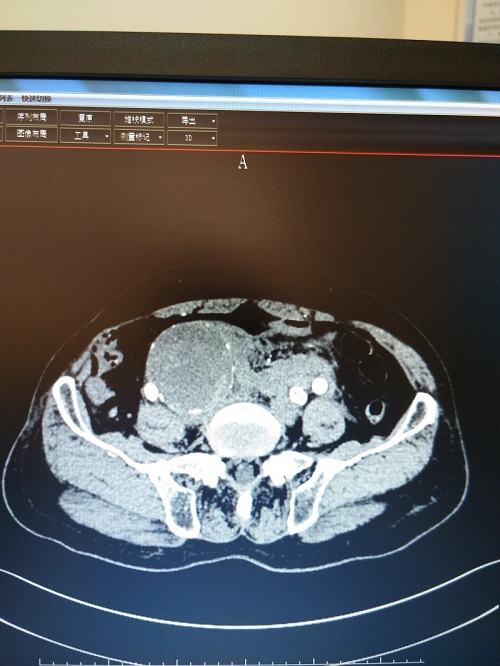

7月4日,胸痛中心接診了一個(gè)經(jīng)外院轉(zhuǎn)來的69歲男性患者,他因?yàn)椤巴话l(fā)腹痛11小時(shí)”轉(zhuǎn)來我院。在外院初步診斷腹主動(dòng)脈-髂動(dòng)脈瘤破裂出血。在我院急診行CT檢查時(shí)疼痛突然加重,大汗淋漓,伴低血壓。CT檢查提示其腹主動(dòng)脈-雙側(cè)髂動(dòng)脈瘤,其中右側(cè)髂動(dòng)脈巨大動(dòng)脈瘤直徑達(dá)7.6cm,伴破裂出血。

術(shù)前CT示右髂動(dòng)脈巨大動(dòng)脈瘤